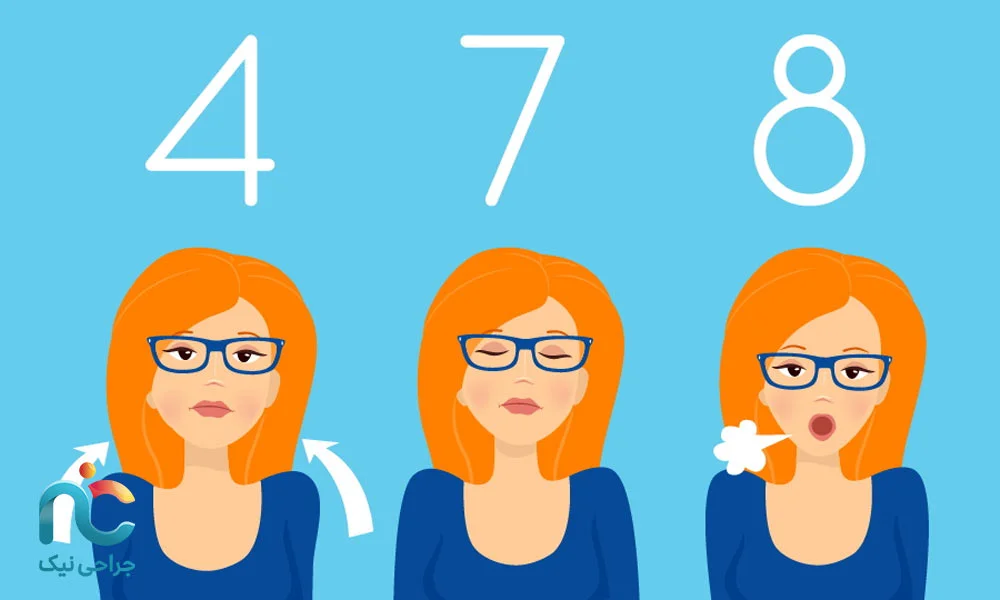

۲. تکنیکهای آرامسازی ذهنی و تنفسی

هر روز چند دقیقه بنشینید، چشمانتان را ببندید، نفسهای عمیق و آرام بکشید: مثلاً چهار ثانیه نفس بکشید، هفت ثانیه نگه دارید، و هشت ثانیه بازدم کنید. این کار روی کاهش ضربان قلب، کاهش فشار خون و آرامش مغز تأثیر دارد. خواب بهتر، کمتر شدن درد پس از عمل و بهبود سریعتر را به همراه دارد (منبع).